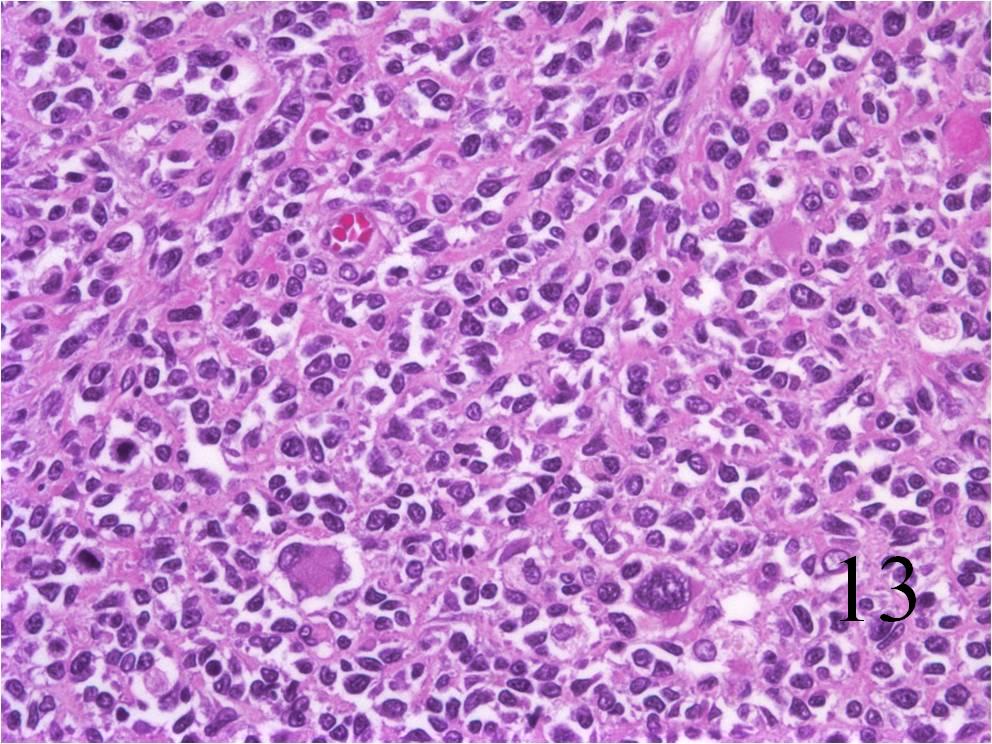

- Embryonal:

- Small round blue cells (Fig. 12-15)

- Round, oval, polygonal cells

- Fibrotic/myxoid stroma

- Rhabdomyoblast: well differentiated will have cross striations